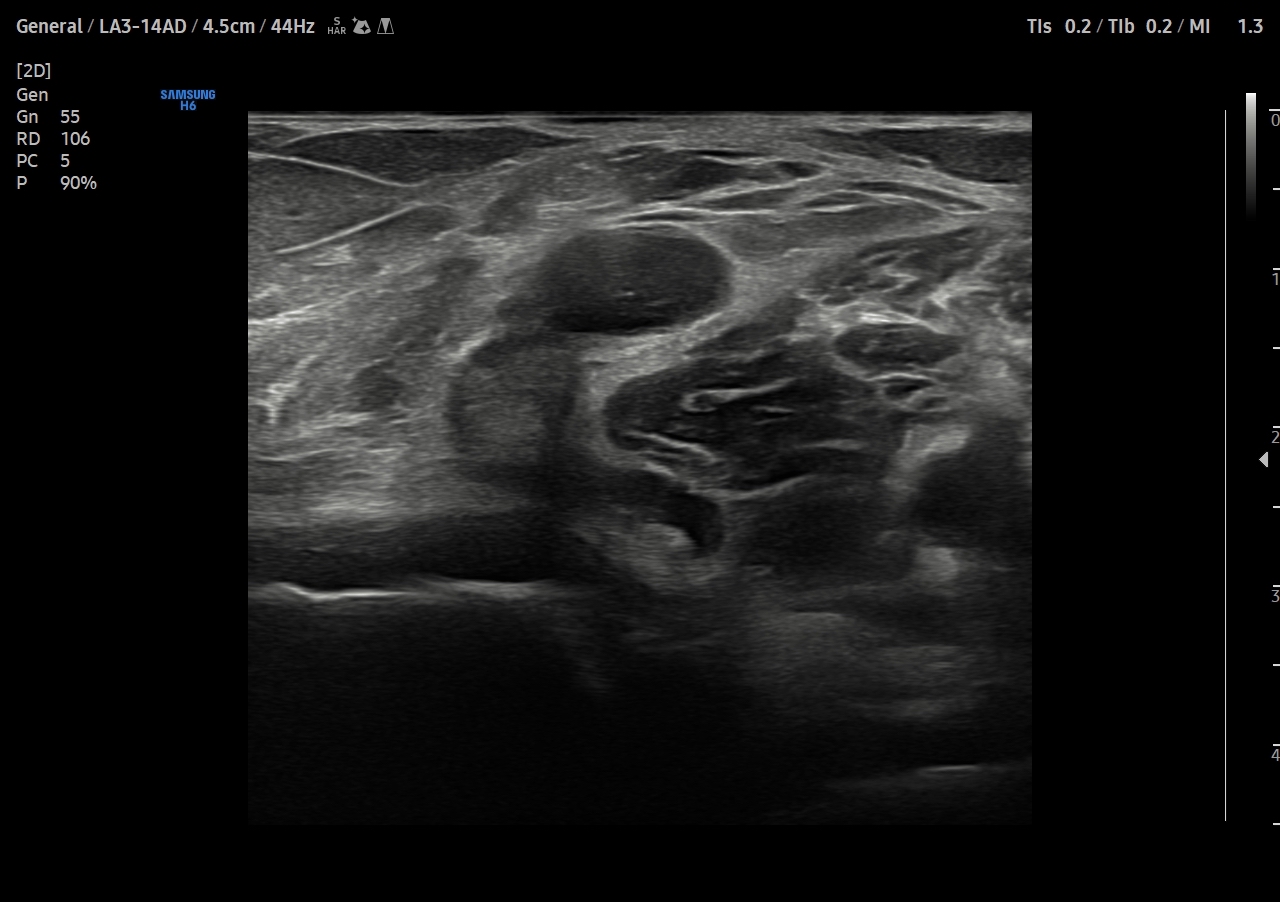

Descripción de los hallazgos ecográficos y las imágenes más relevantes para la resolución del caso

Se explora cara anterior, lateral y medial de rodilla sin hallazgos significativos. En cara posterior se explora el hueco poplíteo donde se visualiza en corte transversal una estructura hipoecoica con la base, el cuello entre el tendón del semimembranoso y el tendón de la cabeza medial del gemelo interno y el cuerpo. Sin signos de complicación. Permeabilidad del sistema venoso profundo.